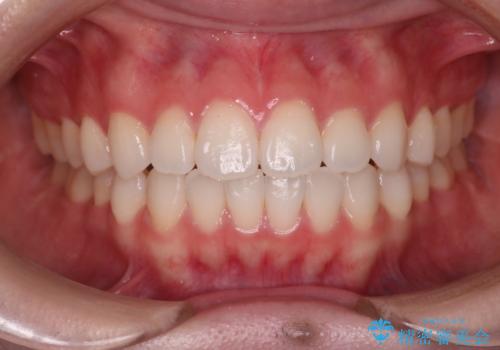

[マルチブラケットで後方移動] ワイヤー矯正で行う噛み合わせの改善